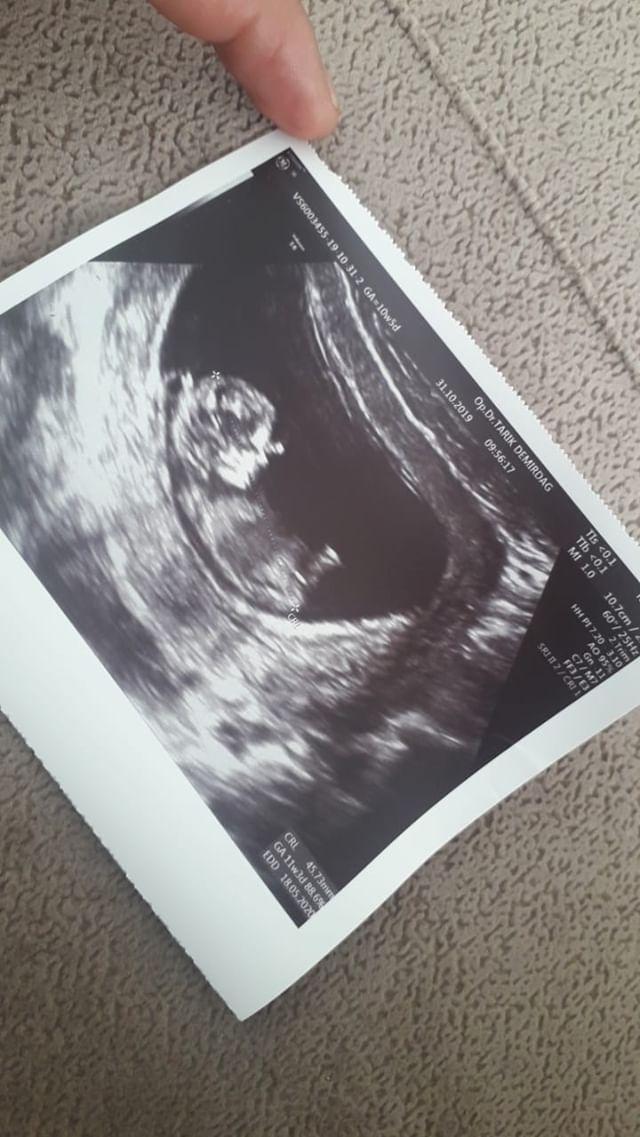

SadmiN ♥ Evli Mutlu Çocuklu ♥ Yönetici 1 Kasım 2019 #15 Merhabalar geç dönüş için üzgünüm net olmamakla bmirlikte bana göre erkek gibi görünüyor Rabbim kucağınıza almayı nasip etsin.

Merhabalar geç dönüş için üzgünüm net olmamakla bmirlikte bana göre erkek gibi görünüyor Rabbim kucağınıza almayı nasip etsin.

SadmiN ♥ Evli Mutlu Çocuklu ♥ Yönetici 1 Kasım 2019 #16 Ben bu tahminimi NUB TEORİSİNE GÖRE YAPTIM incelemek isterseniz aşağıdaki konuya bakın lütfen. https://www.meleklermekani.com/threads/nub-teorisi-ile-cinsiyet-nasil-belirlenir.267709/page-32

Ben bu tahminimi NUB TEORİSİNE GÖRE YAPTIM incelemek isterseniz aşağıdaki konuya bakın lütfen. https://www.meleklermekani.com/threads/nub-teorisi-ile-cinsiyet-nasil-belirlenir.267709/page-32